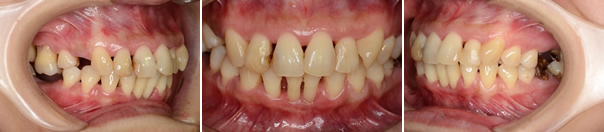

■26歳女性

海外旅行から帰国して、その後、歯を磨き始めた時、突然、歯茎に痛みが走り、肉が腐っているような口臭、口の中の激しい痛みがでました。海外旅行ではかなり疲れたらしいです。喫煙歴あり。

・初診時